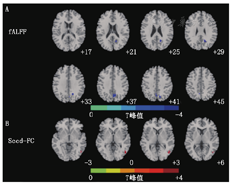

与HC相比,T2DM右侧楔前叶fALFF值显著减低(表1、图1A)。基于fALFF差异显著脑区(右侧楔前叶,峰值坐标为X=18,Y=-60,Z=30)的FC分析示T2DM组右侧楔前叶-右侧颞中回间FC显著升高(表1、图1B)。

2型糖尿病组和健康对照组fALFF组间差异及基于种子点FC分析结果

| 参数 | 脑区 | 体素数 | 峰值MNI坐标 | t峰值 | ||

|---|---|---|---|---|---|---|

| X | Y | Z | ||||

| fALFF | 右侧楔前叶 | 65 | 18 | -60 | 30 | -3.951 |

| Seed-FC | 右侧楔前叶右侧颞中回 | 21 | 48 | -66 | 0 | 4.011 |

注:fALFF为比率低频振幅;Seed-FC为基于种子点的功能连接;MNI为蒙特利尔神经学研究所

注:fALFF为比率低频振幅;Seed-FC为基于种子点的功能连接;T2DM为2型糖尿病;HC为健康对照;FC:功能连接